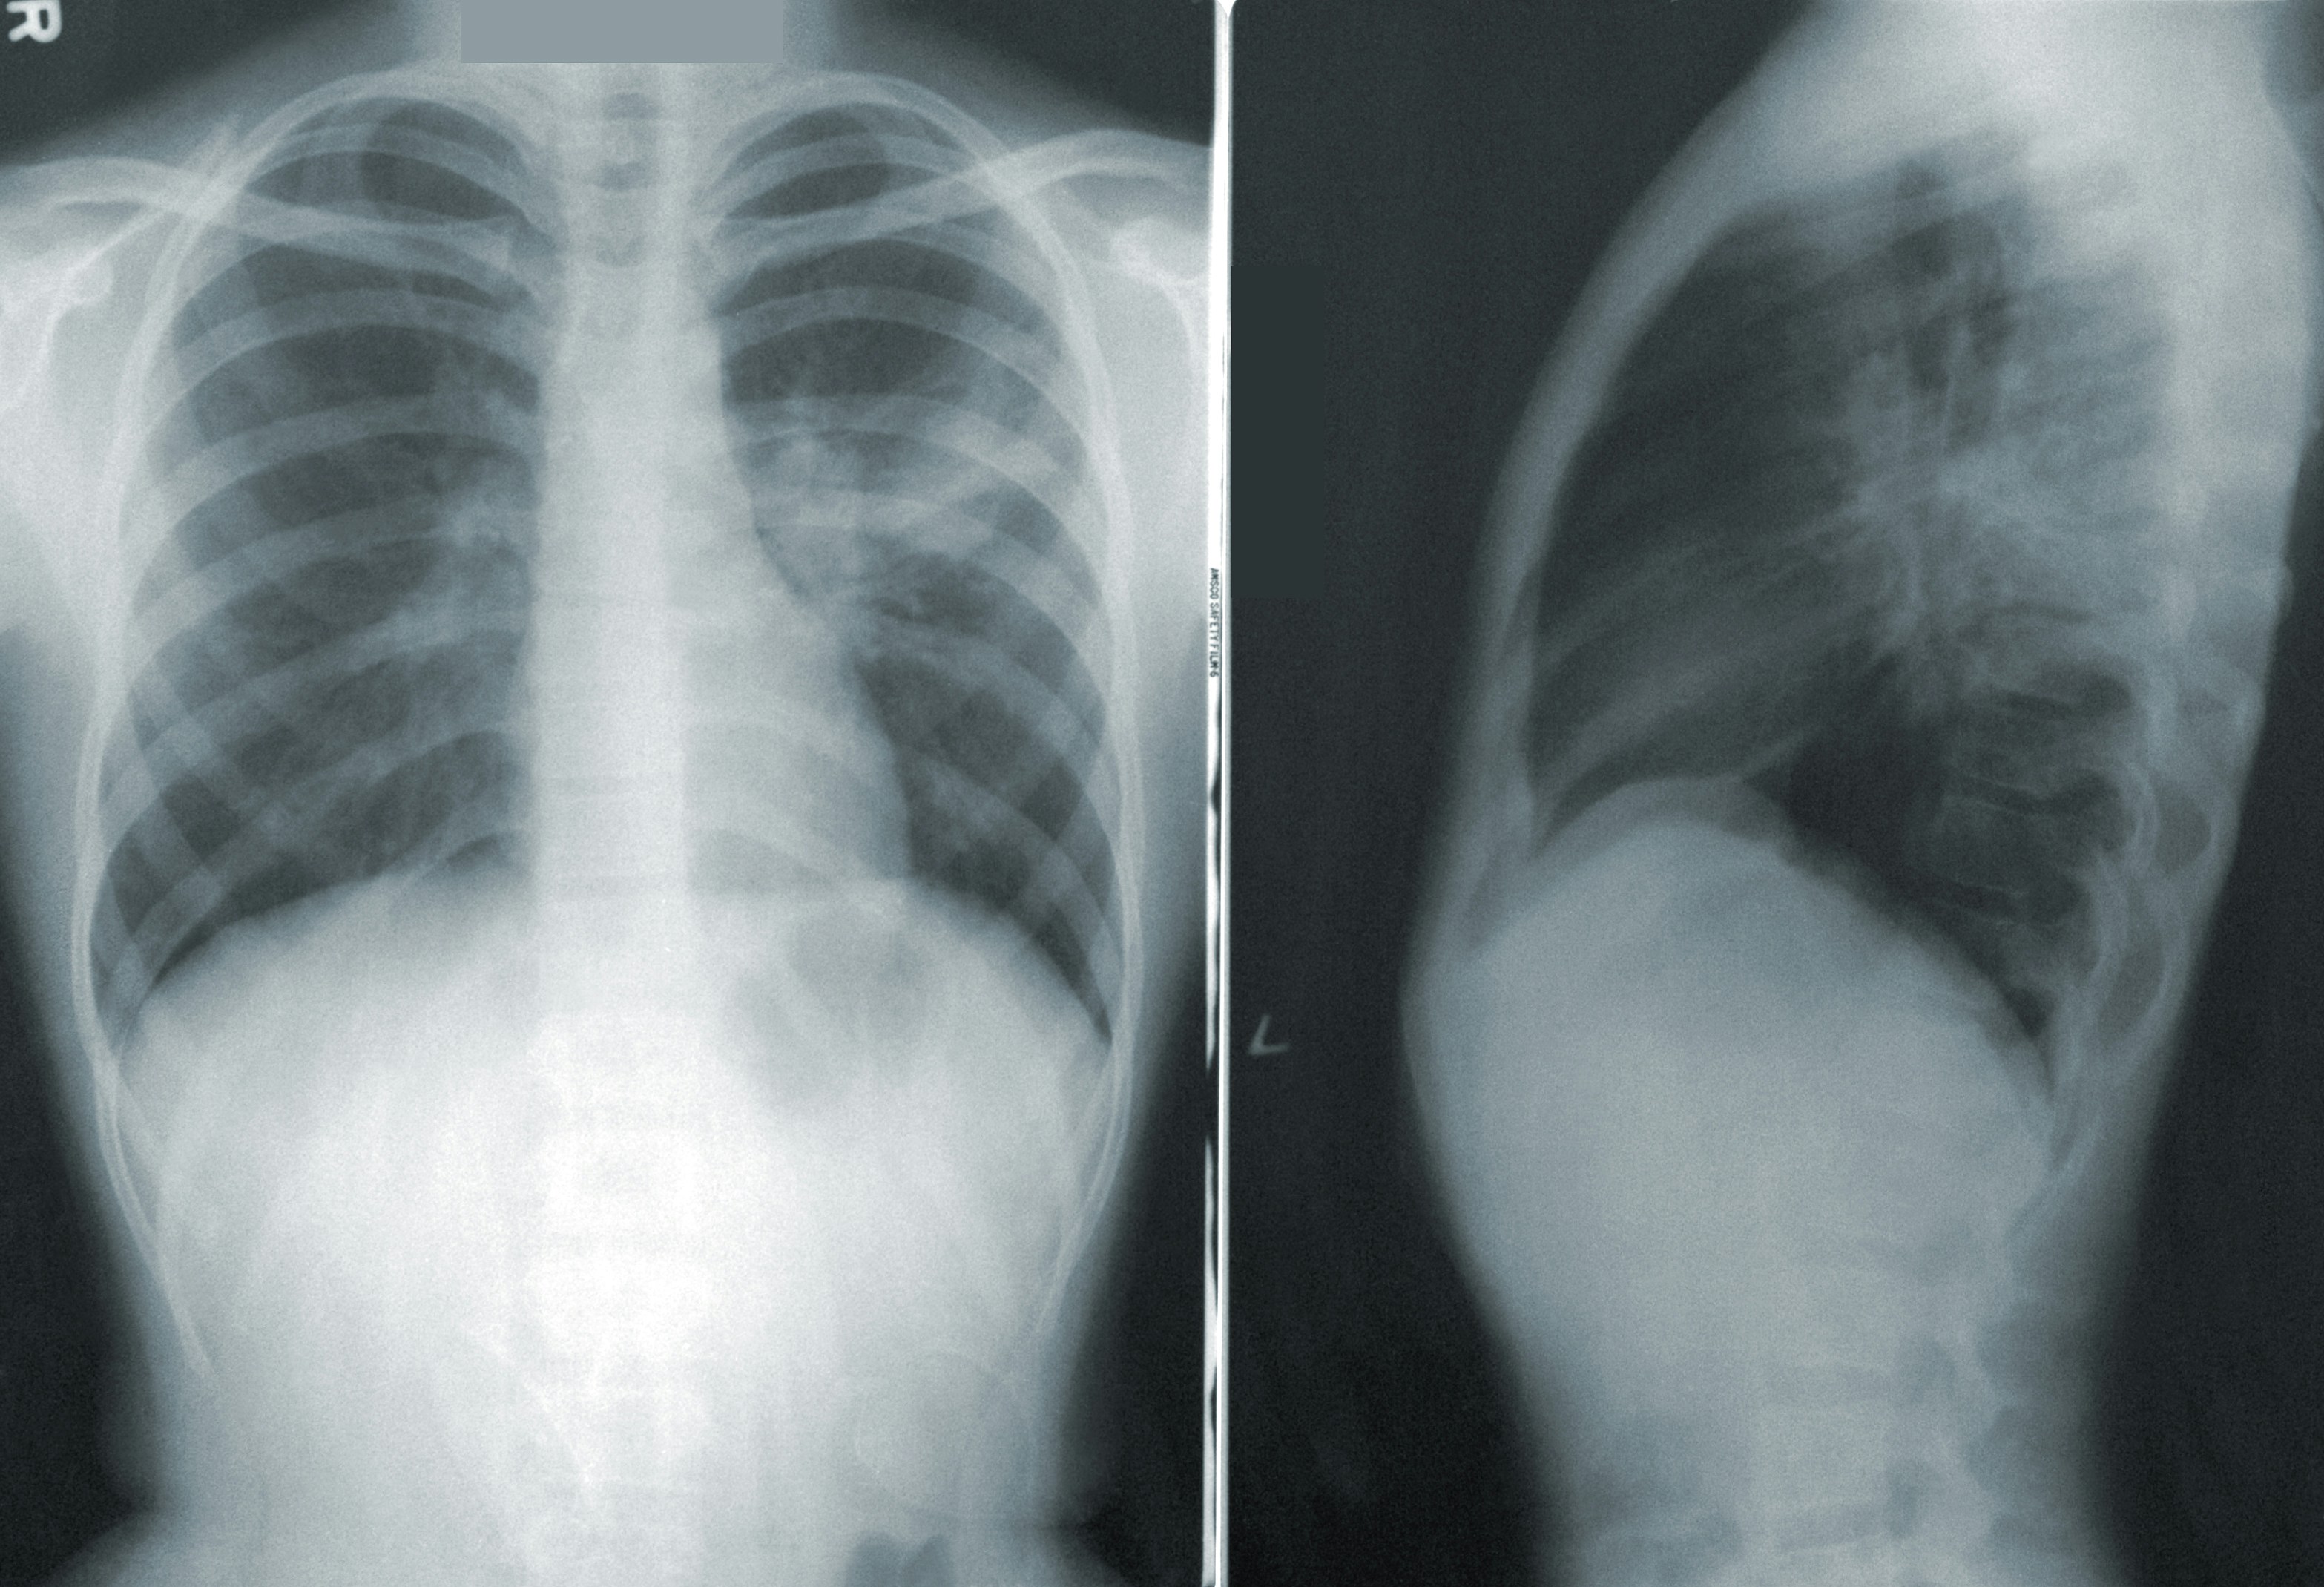

몸통 X레이 사진 :폐렴으로 희뿌옇게 잔가지처럼 염증으로 번진 폐 PV의 급격한 확산: 왜 지금 위험한가?